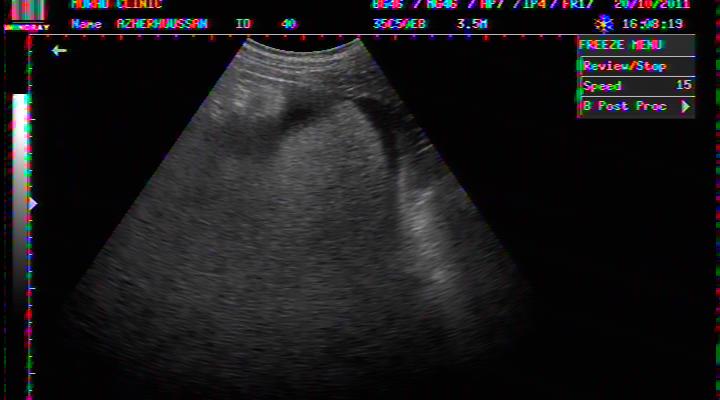

FLUID AROUND LIVER IN DHF

PLASMA FLUID AROUND LIVER IN DHF